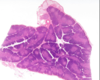

ID Tissue Type and all Structures noted

Lymph Node

- Germinal Center

- Lymph Nodule

- Capsule

- Maybe Trabeculae???

- Sinusoid

- Dr. Jones doesnt know

- Cortex (deep to this is medulla)